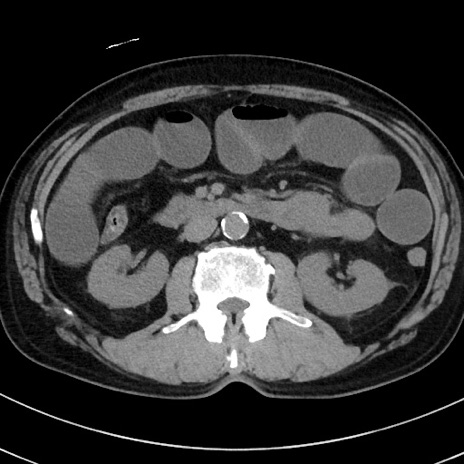

症例38(横断像)

【症例】70歳代 男性

【主訴】腹痛・嘔吐

【現病歴】昨晩より、嘔吐・腹痛あり。今朝になっても嘔吐あり。来院。

【既往歴】心臓バイパス手術、開腹胆摘、腸閉塞

【身体所見】BP 107/71mmHg、HR 116/min、腹部:平坦、軟、下腹部に軽度圧痛あり。反跳痛なし。

【データ】WBC 15100、CRP 0.32